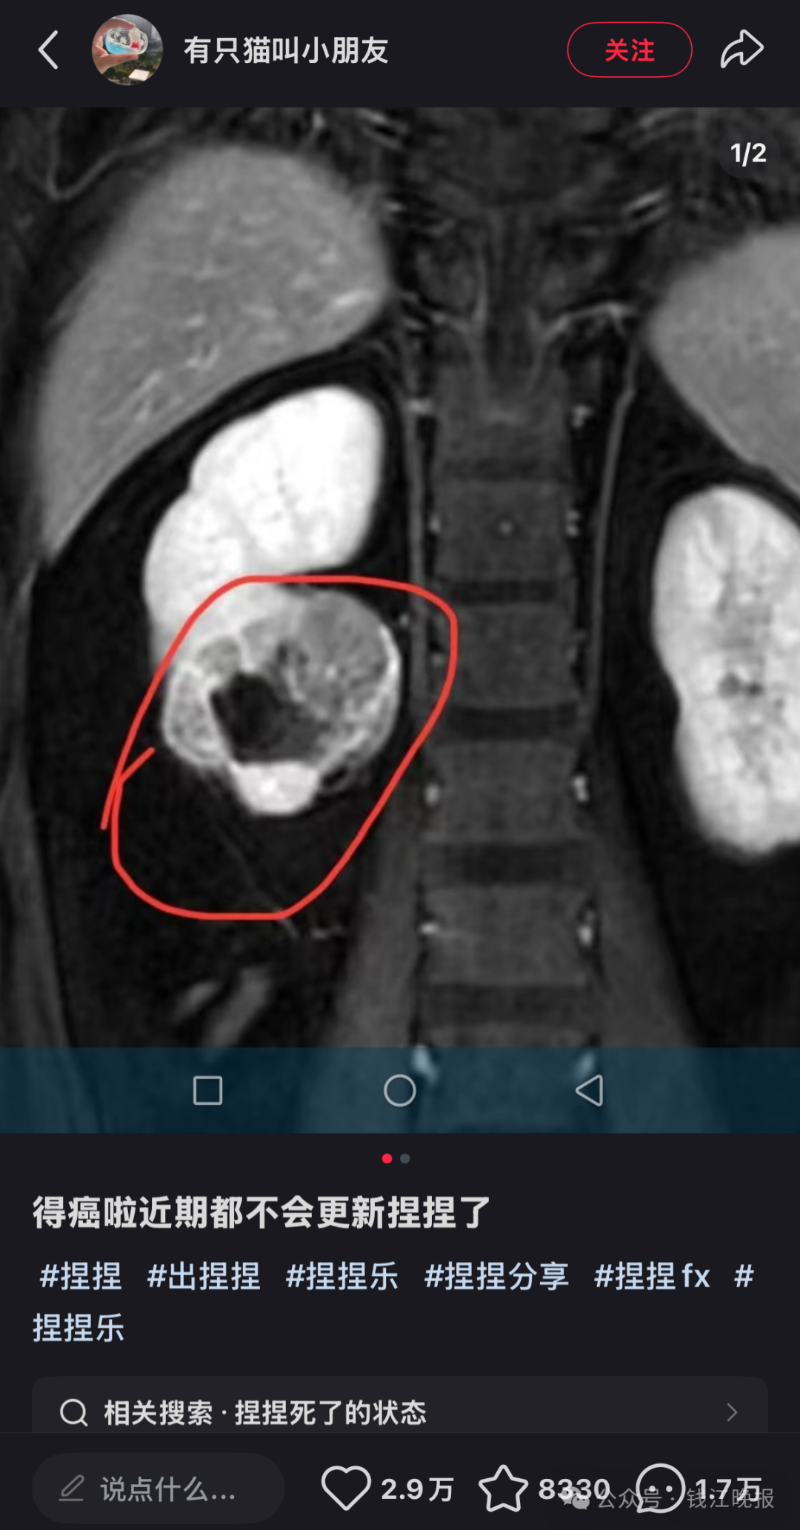

据深圳新闻网报道,该博主在社交媒体上发文透露自己罹患癌症,并宣布将暂时停止更新与“捏捏”玩具相关的视频内容。

该博主在社交平台宣布罹患癌症。图源其账号截图

据了解,其账号长期以展示捏捏玩具的揉捏过程为主,部分限量款产品曾被炒至上千元高价。

此举迅速引发了网友的广泛关注和讨论。虽然该博主在文案中并未提及具体的患癌原因,但在评论区,有不少网友怀疑其患癌原因与长时间接触“捏捏”有关。